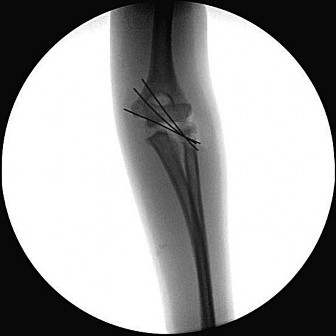

Question 13:

A 6-year-old boy sustains a severe extension-type supracondylar humerus fracture after a fall. Radiographs classify it as a Gartland Type III. The distal fragment is severely displaced posteromedially relative to the proximal shaft. Based on this specific displacement pattern, which of the following nerve structures is at greatest risk of tethering or injury from the proximal fragment?

Correct Answer: Radial nerve

Explanation:

In an extension-type supracondylar humerus fracture, the displacement of the distal fragment dictates the direction of the proximal spike. If the distal fragment is displaced posteromedially, the sharp proximal fragment is thrust anterolaterally, placing the radial nerve at the highest risk of injury. Conversely, if the distal fragment displaces posterolaterally, the proximal spike goes anteromedially, placing the median nerve (and AIN) at greatest risk.